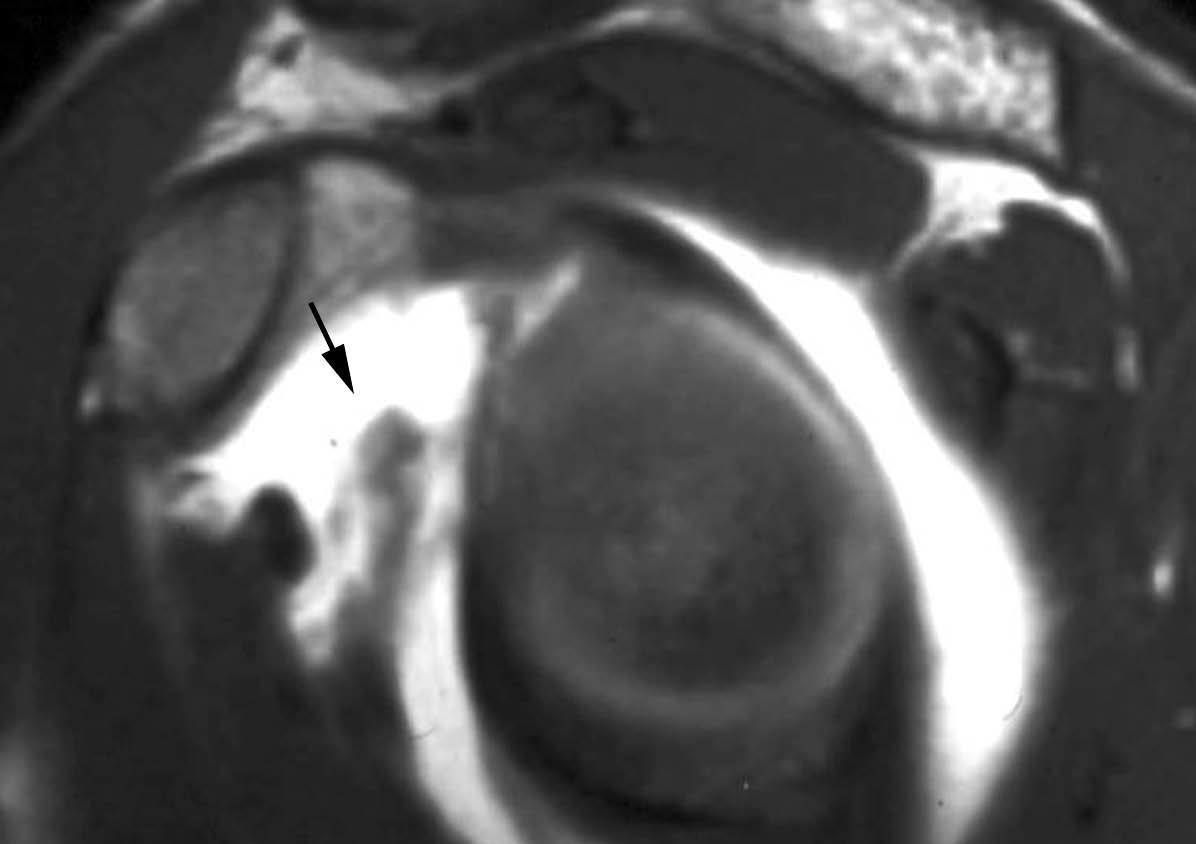

ALPSA (anterior labroliamentous periosteal avulsion)

Al igual que en el apartado anterior, existe también una separación de LG junto con la cápsula y el periostio, pero a diferencia de las lesiones de Bankart o Perthes, el LG se desplaza hacia dentro, por detrás del borde de la glenoides18 (fig. 12). La lesión de ALPSA puede cicatrizar por sinovialización (fig. 12), pero continúa siendo de carácter inestable.

Fig. 12.--ALPSA (anterior labroliamentous periosteal avulsion) agudo (A) y crónico (B). Nótese la separación del labio glenoideo y su desplazamiento posterior y medial por detrás del reborde glenoideo (flecha en A). En una fase crónica el labio glenoideo no se distingue como una estructura separada, sino como un engrosamiento de la unión entre el labio, la cápsula y el periostio (flecha en B).